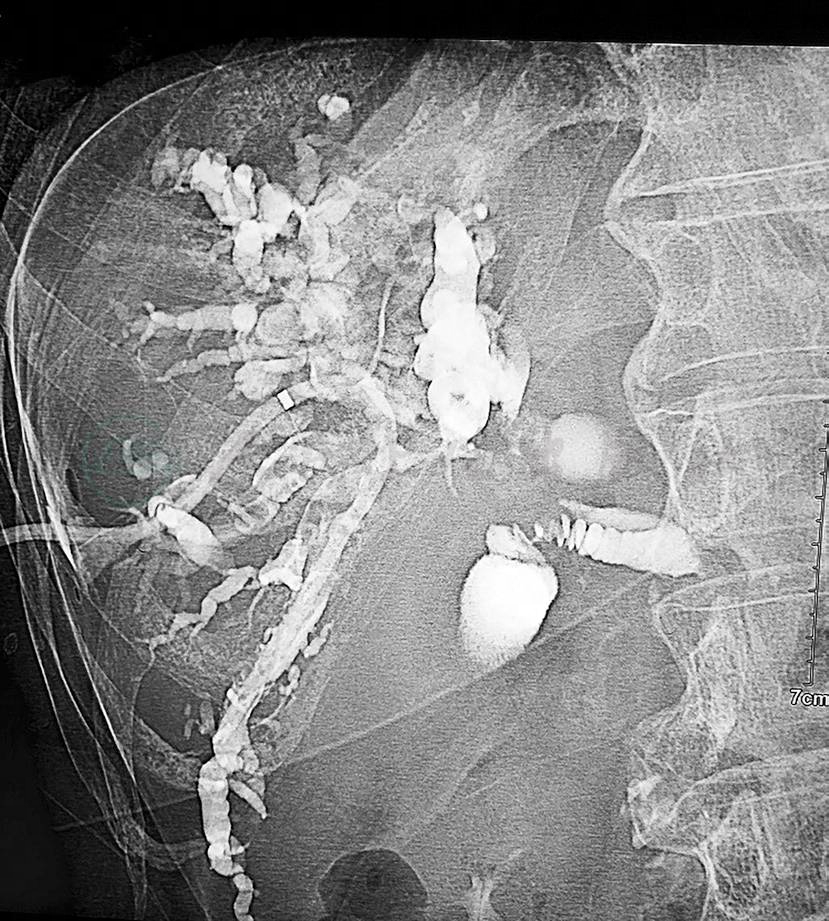

现病史:5个月前进食后出现腹胀,为全腹胀,伴反酸、胃灼热、嗳气,伴耳鸣,不伴头痛,无发热,不伴恶心、呕吐,不伴腹泻,自觉全身皮肤发黄,伴瘙痒,腹胀可自行缓解,黄疸可自行消退,其后进食鱼肉后再次出现腹胀、黄疸。4个月前就诊于我院,GPT 650U/L,GOT 521U/L,TBil 77.3μmol/L,DBil 56.2μmol/L,彩超提示胰腺头颈体部可见低回声包块,大小约7.1cm×2.6cm×2.1cm,边界欠清,回声不均,脾静脉受压,周围胰腺组织偏薄。CT平扫+增强(图1)提示胰头区软组织肿块影,与正常胰腺分界欠清,平扫CT值约40Hu,动脉期明显强化约80Hu,静脉期117Hu。肝内外胆管及胰管扩张。3个月前我院胃镜检查:浅表性胃炎(中度);胃底静脉显露。外院胰腺MRI增强:①考虑胰腺头部占位性病变;②肝内胆管、肝总管扩张,胆总管上段变细、狭窄。转氨酶正常,TBil 77.3μmol/L,DBil 56.2μmol/L。2个月前外院超声检查提示,胰腺后方见条索状低回声,不除外为脾静脉栓塞,不易穿刺。GPT 226U/L,GOT 104U/L,TBil 168.3μmol/L,DBil 147.8μmol/L。外院MRCP提示:胰头、颈部区占位,考虑胰腺癌,包绕肠系膜上动脉,伴低位胆道梗阻。外院影像学会诊:胰头部实性结节,约2.5cm×2cm密度较均匀,伴持续均匀强化,实性假乳头状瘤或神经内分泌肿瘤转变成癌可能性大,建议超声内镜复查。2个月来腹胀,黄疸转为持续并加重,大便间断陶土色,尿液颜色深,皮肤瘙痒严重。

图1 增强CT